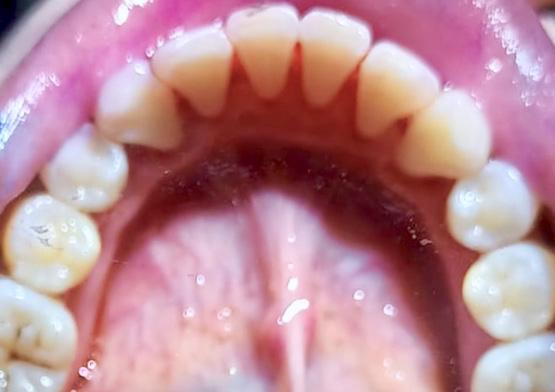

Before Scalling

After Scalling